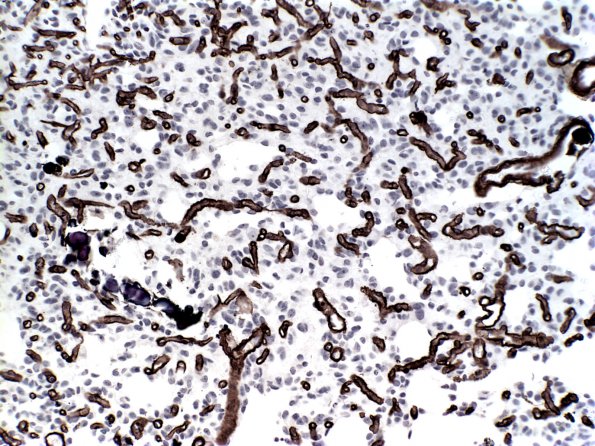

Washington University Experience | NEOPLASMS (GLIAL) | Oligodendroglioma - Histologically Defined (most del 1p19q) | 14E Oligodendroglioma, mild anaplasia (Case 14E) Coll IV

Collagen IV stain demonstrates the extent of proliferation (Coll IV)